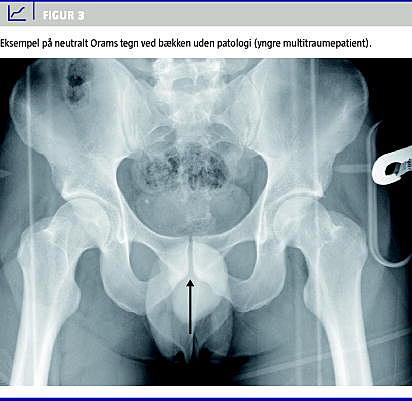

Troværdige og simple noninvasive diagnostiske test til at stille frakturdiagnoser har altid været efterspurgt i klinikken. I den forbindelse har der igennem tiderne været afprøvet mange forskellige metoder -f.eks. påsætning af stemmegaffel og samtidig auskultation på mistanke om hofte-, femurskaft- eller tibiaskaftfraktur [1], simpel perkussion af patella og samtidig auskultation over symfysen for at screene for hoftefraktur [2], og ultralydsskanning af os schaphoideum for at afsløre fraktur [3]. Orams tegn for hoftefraktur er en test, der har været kendt i flere år under forskellige betegnelser [4, 5], men som efter vores opfattelse endnu ikke er blevet regelret evalueret. Det såkaldte Orams tegn (Figur 1 og Figur 2 ) udsiger, at penis peger mod den patologiske side, det vil sige den side, hvor der er hofte- eller bækkenlidelse på et -standard, antero-posteriort (AP) røntgenbillede af bækkenet. Orams tegn har fra Orams tid i det daglige kliniske arbejde - og især ved røntgenkonferencerne - været anset for en værdifuld hjælp til at uddrage så mange oplysninger som muligt af disse røntgenundersøgelser, der foretages på så mange ortopædkirurgiske patienter og helt rutinemæssigt på ikke mindst de mange hoftefrakturpatienter. Selv om overlæge Oram var både dr.med. og dr.phil., har han ikke selv publiceret videnskabelige undersøgelser vedrørende validiteten af Orams tegn. Fra udlandet foreligger der enkelte beskrivelser af enkelte test, der dog er begrænset til udsigelser om hoftefrakturpåvisning [4, 5]. Vi har derfor følt et behov for en stringent videnskabelig evaluering af testens reliabilitet og validitet i en relevant klinisk sammenhæng, idet vi mener, at der kunne være mulighed for helt at undgå røntgenundersøgelse, hvis tegnet viste sig at være validt.

Studiet er retrospektivt og designet som et multibedømmerstudie, men med fokus på reliabilteten af testen hos den enkelte bedømmer er alle styrkeberegninger udført som beregning af det mindste antal test, der kræves for at kunne vise en diagnostisk forskel mellem to test hos en bedømmer [6]. Med et ønske om en sensitivitet for testen på mindst 83%, en specificitet på mindst 60% og en positiv likelihood ratio på 2,96, er der udført styrkeberegning på baggrund af 95%-konfidensintervallet omkring likelihood ratio . Analysen af stikprøvestørrelsen er udført som beskrevet af Simel et al 1991 [7] og er beregnet til 53. For at vurdere testens anvendelighed over for et helt normalt bækkenrøntgen, blev der yderligere medtaget ni optagelser uden frakturer eller anden patologi, hvoraf to optagelser var af kvinder. I studiet indgik således AP-optagelser af bækken fra i alt 62 patienter (60 mænd og to kvinder). Alle røntgenbilleder blev tilfældigt udvalgt fra Århus Sygehus' røntgendatabase af en uafhængig bedømmer og printet på papir af god kvalitet. Alle personhenførbare data, frakturer og kontralaterale side blev maskeret, således at bedømmelsen af røntgenbillederne blev gennemført blindet for alle parametre udover sidebestemmelse af Orams tegn. Fire erfarne mandlige speciallæger i ortopædkirurgi gennemgik billederne hver to gange uafhængigt af hinanden med et passende tidsinterval. For at vurdere en eventuel kønsbestemt observatørbias blev billederne også bedømt en gang af en rutineret ikkeortopædkirurgisk kvindelig speciallæge. Der var således i alt ni observationer af hvert røntgenbillede. Ved evaluering af et røntgenbillede havde bedømmerne fire svarmuligheder: 1) Orams tegn positivt til højre side (Figur 1), 2) Orams tegn positivt til venstre side (Figur 2), 3) Orams tegn neutralt (penis bedømmes at pege lige op eller lige ned i midtlinjen (Figur 3 ) og 4) ikke muligt at bedømme Orams tegn. Validiteten af testen blev evalueret ved beregning af testens sensitivitet, specificitet samt likelihood ratio , idet de frakturer/lidelser i bækken eller hofte, som var diagnosticeret ved den rutinemæssige røntgendiagnostik, blev brugt som gylden standard. Endelig blev reliabiliteten som inter- og intraobservatørvariation evalueret ved beregning af kappakoefficienter. Som database er anvendt Epidata 3.1, og alle analyser er udført i Stata 9.2.